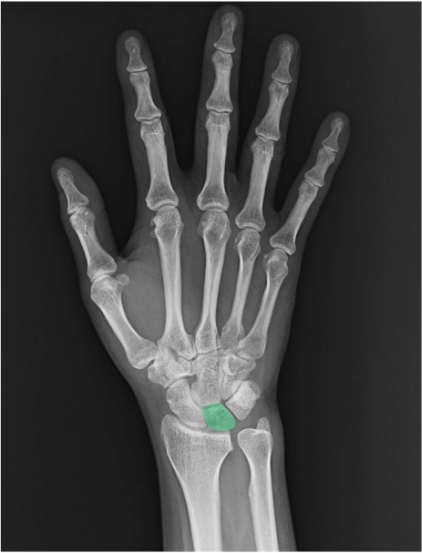

月状骨(lunate)

近位列中央。側面像で橈骨遠位端〜月状骨〜第3中手骨が一直線に配列するか確認(いわゆるアライメント)。半月形の輪郭と骨皮質の連続性に注目。